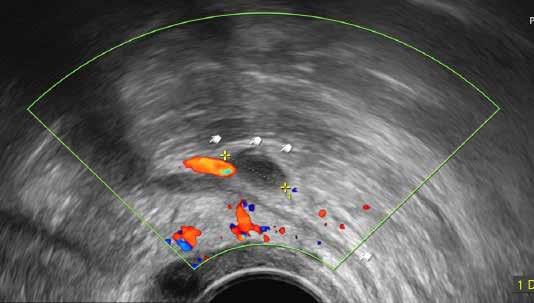

Endometriose-Herde im Darm

In diesem Fall waren die Endometriose-Herde nur auf dem Ultraschall erkennbar, im MRI hin gegen nicht.

Ultraschall Foto von der Operation Makrofoto Pathologie

Unser aus zwei Gynäkologinnen und drei Gynäko logen bestehendes Endometriose-Team ist aus gebildet, im optimalen Fall die kleinen, einige Mil limeter grossen Herde sonographisch darstellen zu können. Bei der systematischen Untersuchung werden zudem nicht nur der Uterus und die Ova rien, sondern die komplette Umgebung der inne ren Geschlechtsorgane im kleinen Becken darge stellt. Dies beinhaltet die komplette Darstellung der Ligamenta sacrouterina, der Tuben, Urethra, Blase, Ureteren und die Rektum-, Sigmawand. Die Beurteilung der Darmwand hat eine beson dere Bedeutung, da bei vermutetem Darmbefall die präoperative Vorbereitung interdisziplinär mit den chirurgischen Kollegen stattfinden muss. Bei bestimmten Fragestellungen (z. B. Cavumform, Junktionalzone) kommt die 3D-Sonographie zum Einsatz. Bei der bimanuellen Untersuchung wird die Muskulatur im kleinen Becken beurteilt, um eine mögliche myofasziale Schmerzkomponen te auszuschliessen. Zudem wird die Reprodu zierbarkeit der Schmerzen überprüft. Wenn die anamnestisch angegebenen Schmerzen an be stimmten Lokalisationen ausgelöst werden kön nen, wird die Therapie-, und Operationsplanung deutlich einfacher.

3D Sonographie

3D Sonographie mit einem kleinen Cavumpolyp und intakter Junztionszone.

Befund am Ureter

Kaudale Ureter-Dilatation bei kleinem Endometrioseherd an der UreterA. uterina Kreuzung